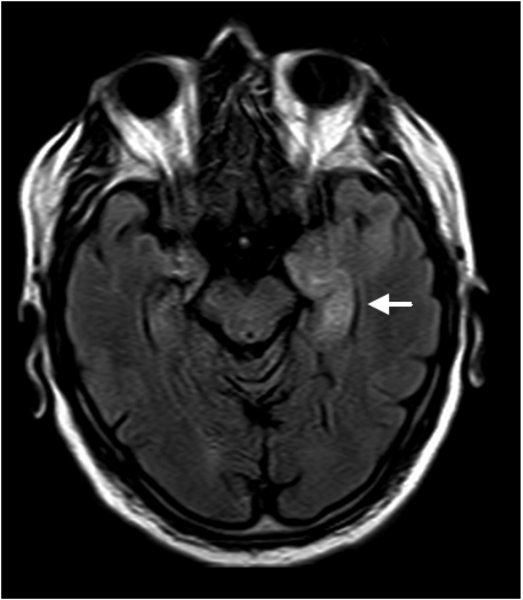

Limbische Enzephalitis

Limbische Enzephalitis - Flair Sequenz